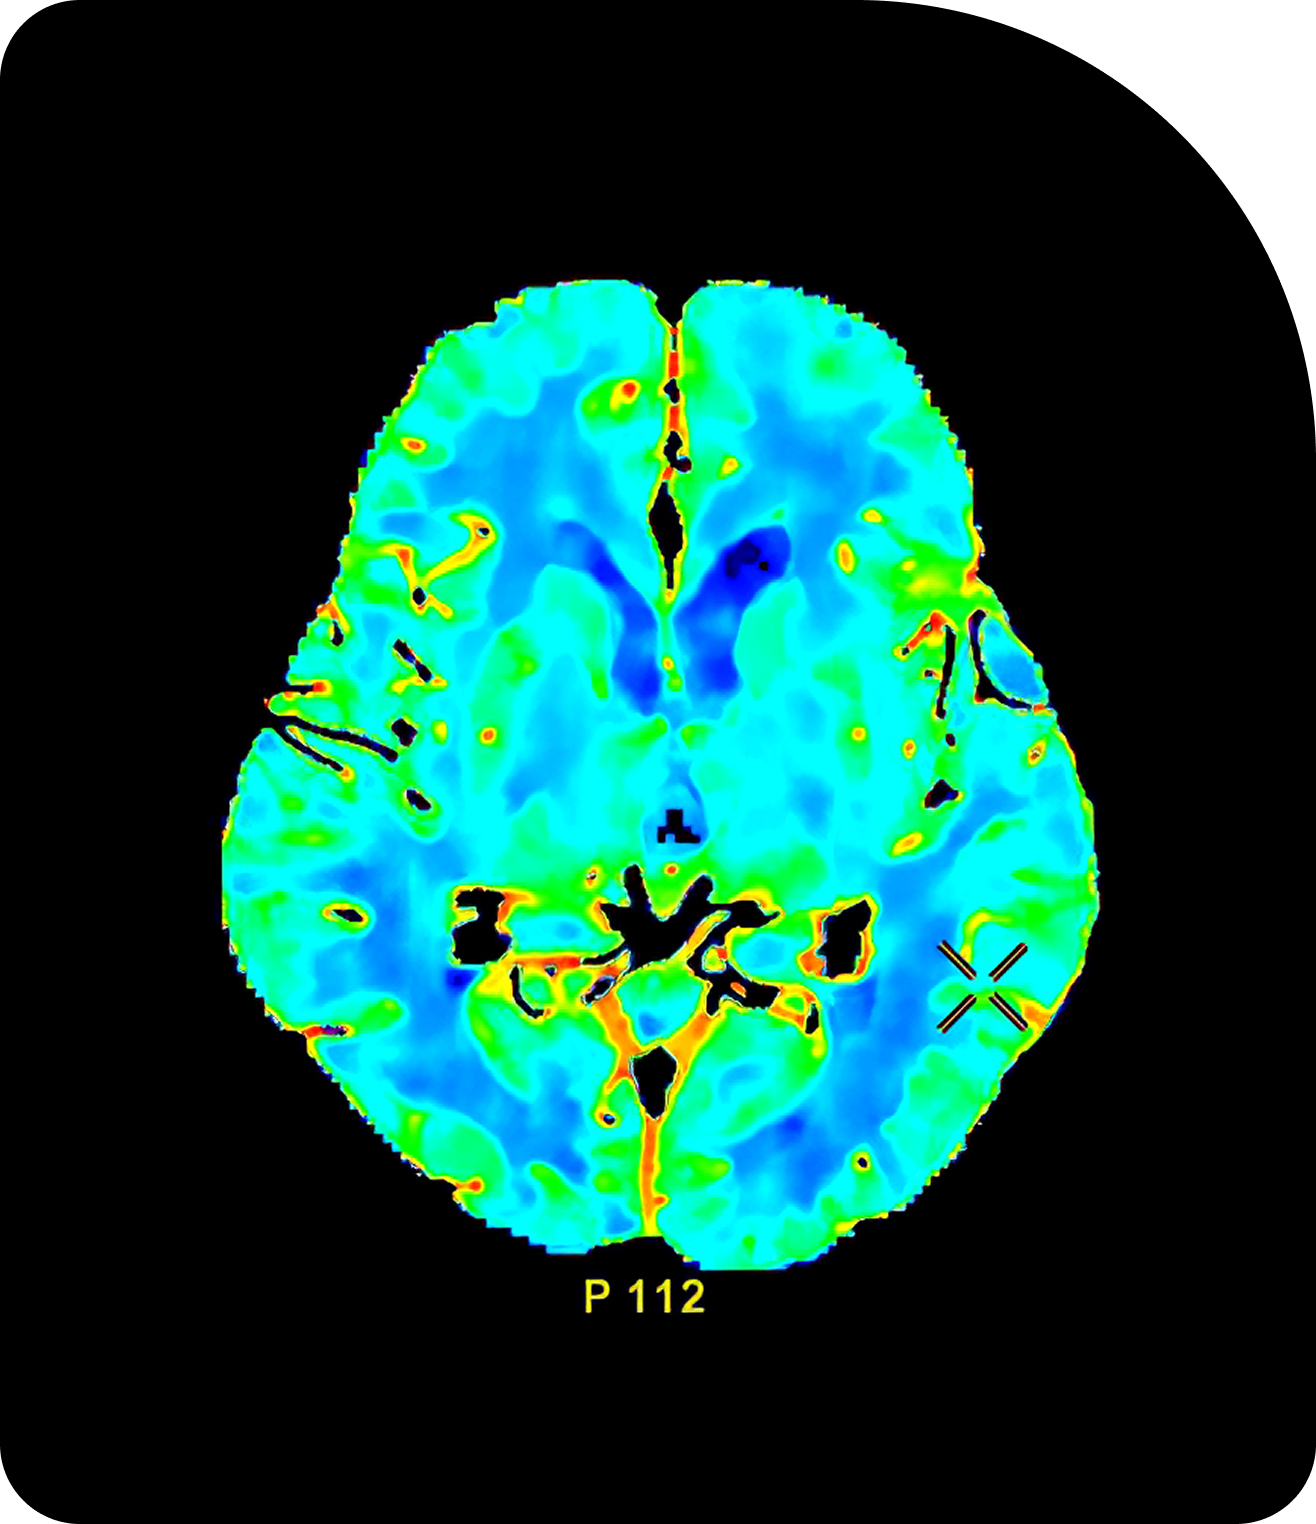

| Cerveau (gliome de haut grade) | UNITED (NCT04726397) ET UNITED-3 (NCT05720078) | Sunnybrook Health Sciences Centre | Faisabilité démontrée des réductions de marge importantes (40-71 %) grâce à la radiothérapie adaptative IRM-Linac. UNITED-3 passe à une thérapie adaptative en deux phases pour le glioblastome.[3] |